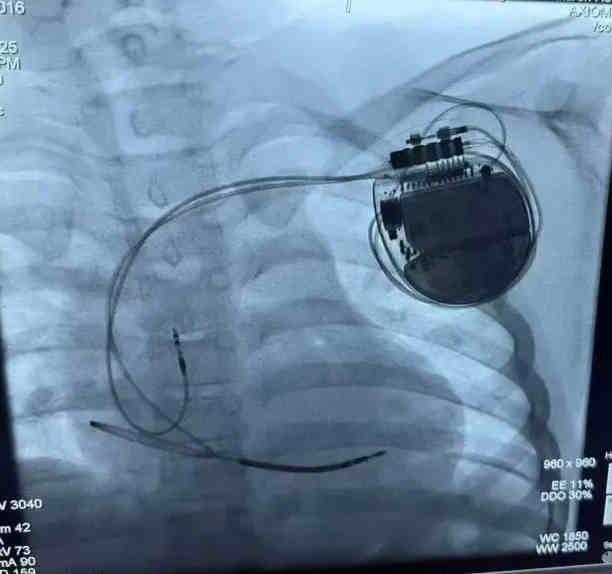

近日,山東大學(xué)附屬兒童醫(yī)院(濟(jì)南市兒童醫(yī)院)心血管內(nèi)科李磊主任團(tuán)隊(duì)成功為一名9歲長(zhǎng)QT綜合征患兒植入新一代帶有VFTA(VF治療保證)的3T核磁兼容植入式心臟復(fù)律除顫器(ICD)。

經(jīng)過(guò)充分的術(shù)前準(zhǔn)備,李磊團(tuán)隊(duì)為小宇實(shí)施了ICD植入術(shù)。手術(shù)在局部麻醉下進(jìn)行,團(tuán)隊(duì)?wèi){借精湛的技術(shù),精準(zhǔn)地將電極導(dǎo)線經(jīng)靜脈植入小宇的右心室,并將ICD脈沖發(fā)生器埋藏于左胸前皮下。整個(gè)手術(shù)過(guò)程順利,耗時(shí)約1.5小時(shí),小宇無(wú)明顯不適。術(shù)后,小宇在醫(yī)護(hù)人員的精心照料下恢復(fù)迅速,精神狀態(tài)良好,食欲也逐漸恢復(fù)。經(jīng)過(guò)一周的觀察與護(hù)理,小宇順利出院,回到了溫暖的家庭懷抱。從此,他再也不用擔(dān)心暈厥的困擾,可以像其他孩子一樣盡情玩耍、快樂(lè)成長(zhǎng)。